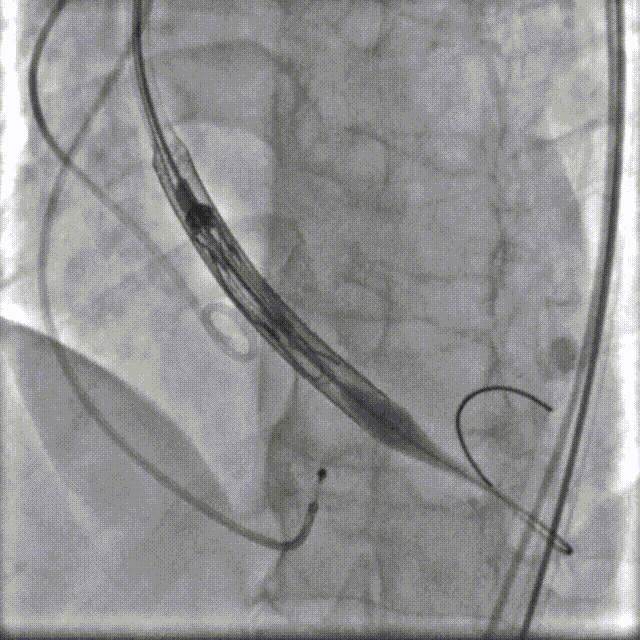

手术过程

其手术过程涵盖LCX支架植入、主动脉根部造影、18球囊预扩、器械进入、释放至紧线状态、松线、器械撤出后造影、下肢动脉造影及术后超声多普勒以下这几个步骤。

• 释放至紧线状态

全球首个,高分子经股主动脉瓣介入术例临床试验成功完成